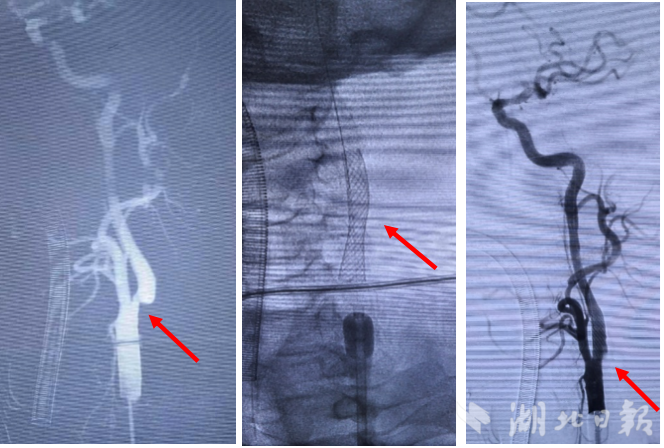

湖北日报客户端讯(记者汪蕾、通讯员孙剑峰)3月29日,宜昌市中心人民医院血管外科再传重磅喜讯:在国内顶尖血管外科专家张玮教授现场指导下,该院副院长梅菲团队成功完成经皮经颈动脉腔内血运重建术(PT-CAS)入组手术,刷新区域微创血管诊疗新纪录。作为湖北省唯一拥有该项目入组资质的临床中心,这一突破标志着该院颈动脉狭窄微创治疗水平跻身全省前列。

手术中,在顶尖专家指导下,梅菲副院长团队精准定位、精细操作,顺利建立起逆向血流保护通道,如同给手术装上了“安全滤网”。

在实时影像监护下,支架精准到位、完美释放,全程生命体征平稳。手术后,杨先生肢体肌力正常,恢复情况十分理想。

由安贞医院团队原创研发的PT-CAS微创术式,采用近端球囊阻断+逆向血流保护方案,可高效拦截斑块碎屑,显著降低围手术期卒中风险,在高龄、心肺功能差、颈部解剖复杂等患者中优势突出。

相比传统术式,该技术具备微创小切口,大幅降低颅神经损伤风险、无逆流盲区,斑块捕获更彻底、不经主动脉弓,特别适合血管迂曲、弓部斑块等高危复杂患者等三大优势。